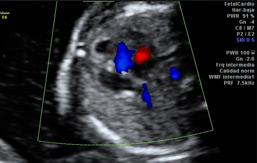

Ecografías de la semana 27 de embarazo

Ecografía semana 27: corte del corazón fetal. La imagen del corazón muestra los dos ventrículos y las dos aurículas mediante la tecnología de Doppler color.